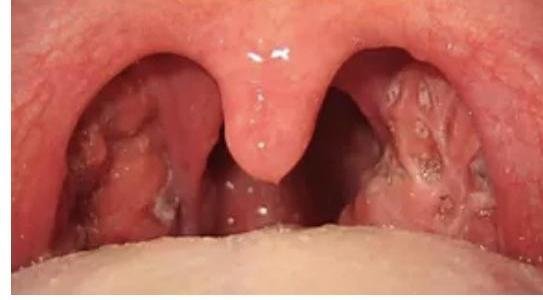

# FARINGOAMIGDALITIS AGUDA ## DEFINICIÓN La faringoamigdalitis es una infección de la faringe y amígdalas que se caracteriza por garganta roja de más de cinco días de duración, afecta a ambos sexos y a todas las edades, pero es mucho más frecuente en la infancia. **FARINGOAMIGDALITIS DE REPETICIÓN**: **3 o más episodios** de **Faringoamigdalitis Bacteriana** en **1 año**, durante los últimos **3 años** - Indicación de **AMIGDALECTOMÍA**. ## ETIOLOGÍA 1. VIRAL (90 %) 2. Estreptococo Beta Hemolítico del Grupo A (EBHGA) solo el 15 % ## EPIDEMIOLOGÍA * Una **infección verdadera** es muy diferente a un enrojecimiento por **resfriado de vías respiratorias altas** (GPC). * Es uno de los **motivos de consulta** más solicitados en **primer nivel de atención**. * Su **manejo** generalmente es en **primer nivel de atención**. * El **incumplimiento al tratamiento** y la **automedicación** propicia las **resistencias bacterianas**. ## FACTORES DE RIESGO * **Tabaquismo activo y pasivo** * **Exposición a enfermos de amigdalitis** (**asintomáticos con Pyogenes**) * **Cambios bruscos de temperatura** * **RGE** (Reflujo gastroesofágico) ## CLÍNICA * **Exudado blanquecino** + **Hipertrofia en amígdalas** * **Adenopatía cervical** * **Ausencia de rinorrea y tos** * **Fiebre >38.0 °C** **Origen viral**: **rinorrea**, **tos húmeda**, **disfonía** y **conjuntivitis**.  # DIAGNÓSTICO ## GOLD STANDARD: CULTIVO FARÍNGEO * Se utiliza para **confirmar el diagnóstico** y su **sensibilidad es 90-95 %**. * Se recomienda en **pacientes que no mejoran con el tratamiento**. ## 1ra ELECCIÓN: CLÍNICO * Es posible **establecer un diagnóstico** e **iniciar antibiótico empírico** si se encuentran los **4 síntomas clásicos** y el paciente tiene una **presentación tóxica**. ## ANTÍGENO RÁPIDO DE INMUNOENSAYO * Se utiliza para **identificar el EBHGA**. * Tiene una **sensibilidad de 61-95 %** y **especificidad de 88-100 %** (se debe **complementar con un cultivo**). * Es una **prueba rápida y barata**, pero su **uso rutinario no genera grandes cambios en la prescripción**. ## CRITERIOS DE CENTOR MODIFICADOS POR MCISAAC | SÍNTOMAS | PUNTUACIÓN | | :--------------------------- | :--------: | | Fiebre >38°C | 1 | | Exudado o Hipertrofia Amigdalar | 1 | | Adenopatías Laterocervicales Dolorosas | 1 | | Ausencia de Tos | 1 | | **EDAD** | | | - 3-14 años | 1 | | - 15-45 años | 0 | | - >45 años | -1 | | Puntos | Probabilidad EBHGA | | :----: | :----------------: | | 5-4 | 50 % | | 3 | 35 % | | 2 | 17 % | | 1 | 10 % | | -1-0 | 1 % | # TRATAMIENTO ## ORIGEN VIRAL La mayoría de las veces (alrededor del 90 %) la **etiología es viral** y requiere **manejo sintomático**. ## 1ra ELECCIÓN: PARACETAMOL / IBUPROFENO Son los **más seguros y eficaces** que los **antibióticos** contra los **síntomas**. En adultos, el **dolor en la deglución** puede ser incluso tratado con **lidocaína spray o solución**. ## ORIGEN BACTERIANO El **uso de antibiótico** en **presencia de estreptococos beta del grupo A** **acorta el curso de la enfermedad**: ## 1ra ELECCIÓN: Amoxicilina - Ácido Clavulánico 500 mg cada 8 horas x 10 días / PENICILINA Si se dispone de PENICILINA, puede aplicarse el siguiente esquema: \begin{gathered} \text { Penicilina Compuesta 1,200,000 UI (1 cada 12 horas } \times 2 \text { dosis) } \\ + \\ \text { Penicilina Procaínica 800,000 UI (cada 12 horas)} \end{gathered} Otros Esquemas Recomendados: * Cefalosporina de 1ª Generación x 10 días * Clindamicina 600 mg / día en 2-4 dosis x 10 días ## 2ra ELECCIÓN: ERITROMICINA / CEFALOSPORINA DE 1ª GENERACIÓN * Indicado en alergia a la Penicilina. ## TRATAMIENTO DE ERRADICACIÓN **Inicia 9 días después** de la enfermedad aguda y **continua por 10 días**. Se debe **realizar cultivo faríngeo 7 días después** de terminar el tratamiento inicial. **Penicilina Benzatínica 1,200,000 UI cada 21 días** a partir de la **primera aplicación de la Penicilina compuesta** (utilizada en el tratamiento inicial) x **3 meses**. ## NO FARMACOLÓGICO 1. **Incremento de ingesta de líquidos** 2. **Mantener alimentación adecuada** 3. **Gárgaras con agua salada bicarbonatada** (1/4 de cucharada en un vaso con agua). # REFERENCIA ## Envío URGENTE A 2º NIVEL: * **Epiglotitis** * **Absceso periamigdalino o retrofaríngeo** * **Dificultad para respirar** * **Estridor** * **Disfagia** * **Sialorrea** ## Envío ORDINARIO A 2º NIVEL: * **Cultivo positivo post-tratamiento de erradicación** * **Cuadros recurrentes** por **S. aureus productor de Betalactamasa**, **ausencia de flora bacteriana**, **pobre respuesta al tratamiento**. ## PRONÓSTICO * El **principal objetivo del tratamiento** es **prevenir el desarrollo** de la **FIEBRE REUMÁTICA**. * **Después de iniciar el tratamiento** los **síntomas ceden a las 48 - 72 horas**. * El **tratamiento temprano para EBHGA** **reduce el tiempo de síntomas a 1 -2 días** (**típicamente dura 3 - 7 días**). ## COMPLICACIONES **ABSCESOS PERIAMIGDALINOS**: se considera un **absceso profundo del cuello**. * **FR**: **mal estado de higiene bucal**, **DM**, **Enfermedad Autoinmune**, **VIH**. * **RX**: **útil para mediastinitis** y **derrame pleural** (**poco específico para un absceso retrofaríngeo**). - **ABORDAJE**: **TAC** + **Punción** + **Drenaje** + **Antibióticos IV**. **1ra elección**: **Penicilina Procaínica 800,000 UI c/12 horas** + **Metronidazol 500 mg VO por 10 días**. Este esquema se indica si el **manejo se realiza en 1er nivel**. Si no muestra una **evolución favorable** se **envía a 2º - 3er nivel** con: **1ra elección**: **CEFTRIAXONA 1-2 g c/8 horas** + **Clindamicina 600 mg c/6 horas o Metronidazol**.